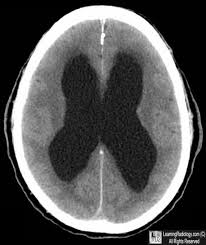

Hydrocephalus is a condition where cerebrospinal fluid (CSF), the fluid that surrounds and protects the brain and spinal cord, builds up inside the brain. This can increase pressure on the brain and cause a variety of symptoms.

CT scan or MRI scan of the brain to see fluid buildup